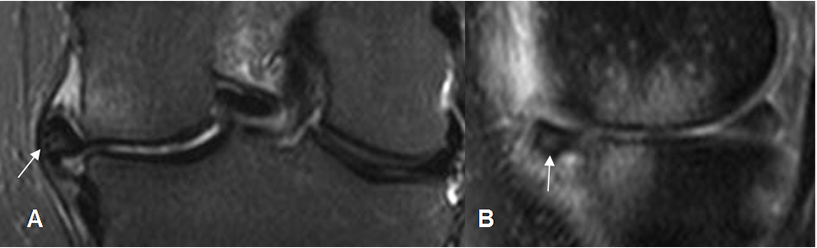

Fig 84. Falsa ruptura meniscal.

A y B: RM sagital en T1. En A hay imagen en sentido oblicuo en el cuerno anterior, que se comunica con la superficie articular superior, sugestiva de ruptura meniscal. En el corte sucesivo B, se aprecia que la imagen está compuesta por el cuerno anterior del menisco (Flecha delgada) y el ligamento transverso (Flecha gruesa) y no corresponde a ruptura.

Fig 85. Falsa ruptura meniscal.

A y B: RM sagital en T1. Imagen en sentido vertical, sobre el cuerno posterior del menisco externo en A, que se comunica con la superficie articular superior, compatible con ruptura meniscal. En el siguiente corte B, esta imagen está formada por el borde del menisco y el tendón poplíteo, correspondiendo a falsa ruptura.